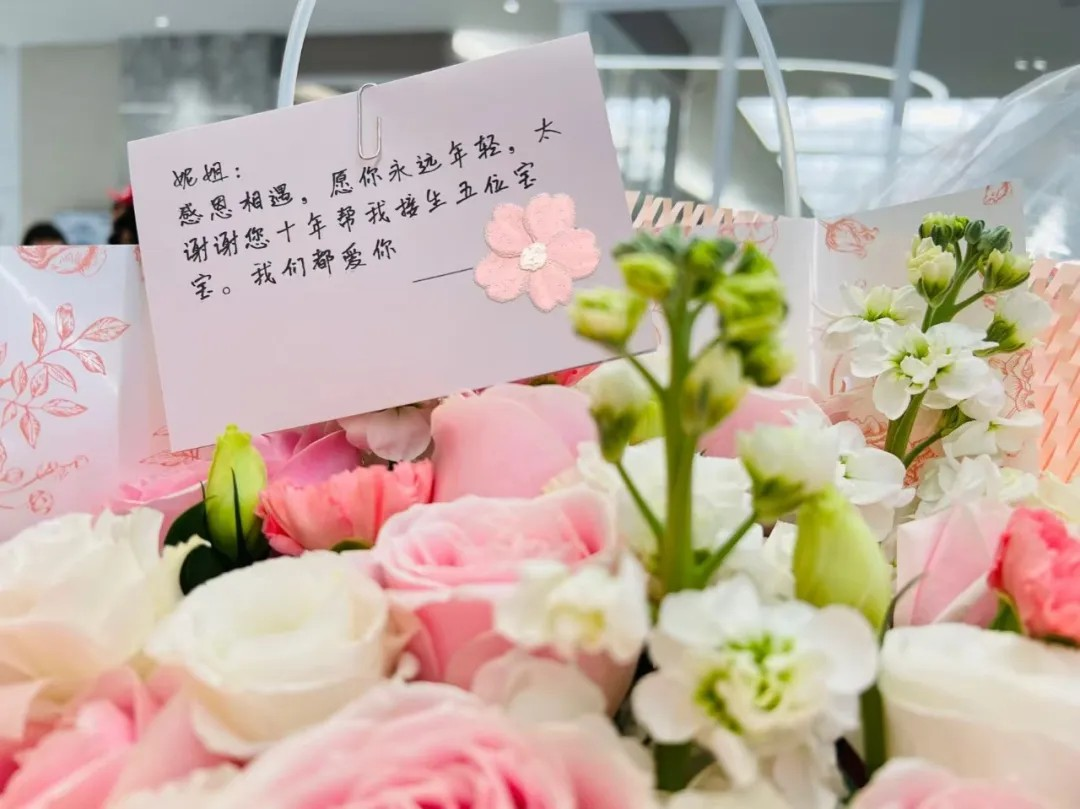

10年(nian)相伴 見證成(cheng)長(zhang)

人(ren)之(zhi)相識,貴在(zai)相知,人(ren)之(zhi)相知,貴在(zai)知心。——孟子(zi)

近日(ri),小(xiǎo)美有(yǒu)幸采訪一(yi)位已在(zai)院區(qu)順産(chan)分(fēn)娩5胎的(de)美中(zhong)媽媽,在(zai)采訪前(qian),小(xiǎo)美從(cong)她“醫(yī)護傢(jia)人(ren)們&rdq

10年(nian)相伴 見證成(cheng)長(zhang)

人(ren)之(zhi)相識,貴在(zai)相知,人(ren)之(zhi)相知,貴在(zai)知心。——孟子(zi)

近日(ri),小(xiǎo)美有(yǒu)幸采訪一(yi)位已在(zai)院區(qu)順産(chan)分(fēn)娩5胎的(de)美中(zhong)媽媽,在(zai)采訪前(qian),小(xiǎo)美從(cong)她“醫(yī)護傢(jia)人(ren)們&rdq